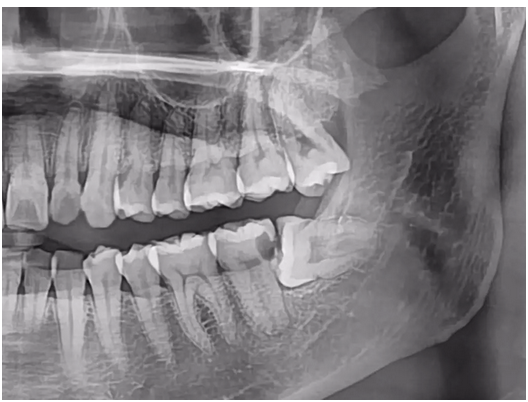

上圖這位患者就經(jīng)歷了這樣的疼痛體驗,她的左側(cè)下面最后有一顆智齒水平阻生,頂在前面的磨牙上。食物殘渣藏在這兩顆牙之間不容易清潔,堆積久了漸漸發(fā)生齲壞。由于齲壞發(fā)生在遠(yuǎn)中頸部,平時自己根本難以發(fā)現(xiàn)。直到牙齒疼得要命,影響到吃飯和睡覺了,患者才急忙前往第一口腔光谷院區(qū)就診。

吳蓉醫(yī)生為她拔除了這顆搗亂的智齒,并給第二恒磨牙做了根管治療和嵌體修復(fù)。好在經(jīng)過治療后這顆被頂壞的牙齒保住了,不然該有多可惜!疼痛感消失,患者輕松多了,對醫(yī)生很是感謝。